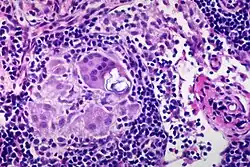

Schaumann body

In pathology, Schaumann bodies are calcium and protein inclusions inside of Langhans giant cells as part of a granuloma.